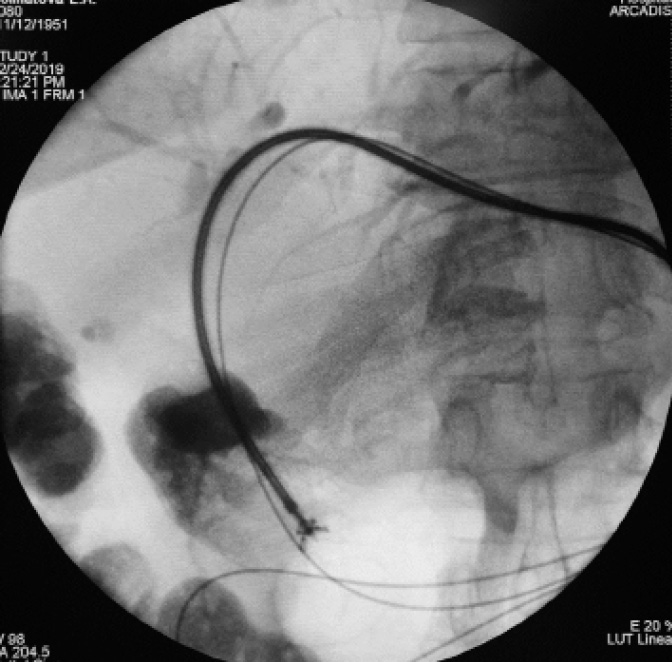

Рис. 4. Чрескожная чреспеченочная эндобилиарная фотодинамическая терапия холангиокарциномы. Стрелкой указан кончик микрокатетера (конец процедуры)

При этом использовали фотосенсибилизатор второго поколения «Радахлорин®», который вводили за 2 ч до светового воздействия. Облучение опухоли проводилось с использованием гибкого оптоволоконного световода через интродьюсер 7 F в непрерывном режиме, с длиной волны 662 нм и мощностью излучения 1 W. Общая доза облучения составила 700 Дж, суммарная экспозиция — 11 мин 40 с. По завершении сеанса восстанавливалось наружновнутреннее холангиодренирование. Послеоперационный период гладкий.